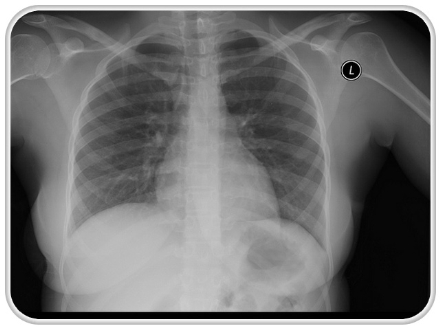

با بروز علائم، احتمالا پزشک درخواست عکس رادیولوژی یا آزمایشهای تصویری دیگری را میکند. ممکن است آزمایش مخاط سینه لازم باشد. اگر آزمایشها وجود سرطان را تایید کردند به احتمال زیاد نمونهبرداری از بافت ریه هم انجام میشود. پس از بررسی نمونه، پاتولوژیست میتواند بگوید که آیا تومور سرطانی است یا نه و اگر جواب مثبت بود نوع آن را مشخص کند.